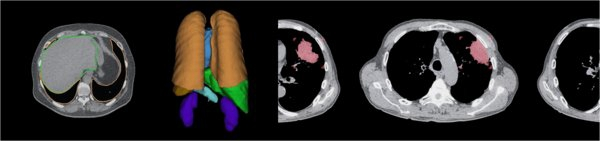

区域识别与CAD

富士胶片的人工智能技术REiLI,来源于最先进的人工智能技术与其传统优势的图像处理技术的结合。富士胶片计划凭借REiLI实现未来诊断流程。在成像检查后,REiLI将能识别器官的形状,并发现与正常组织结构不同的部分,针对检测到的特征,它会根据疾病和人体部位对患者进行分类,并向相应领域中最适合的放射科医师发出通知。放射科医师收到提醒后开始阅读研究报告,为检测到的特征做注释以便于识别。REiLI还能根据数据库列出患者潜在的疾病状况,以便放射科医师能够有效地进行诊断。